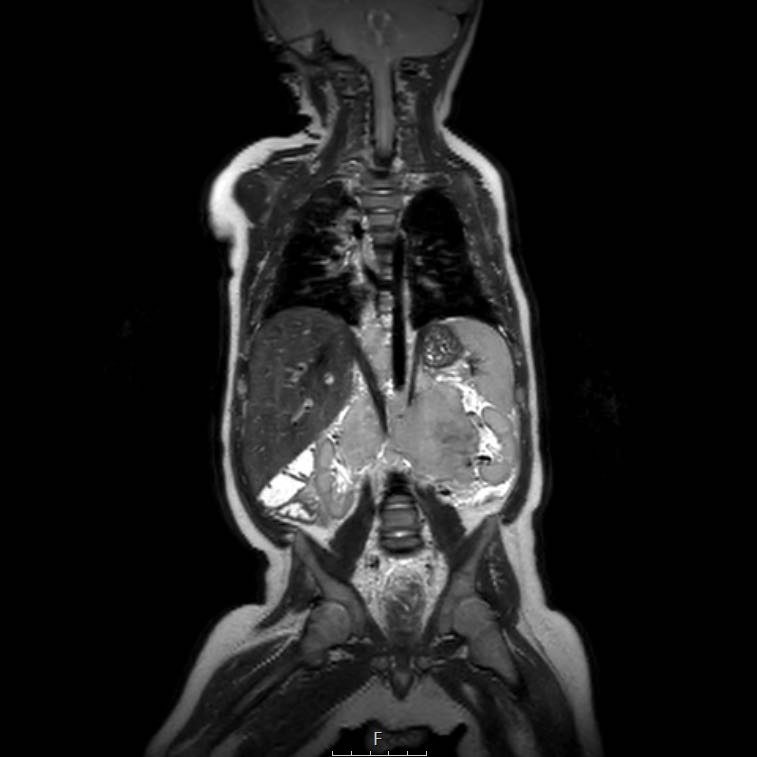

Cuộn qua chuỗi ảnh T2 theo mặt phẳng coronal.

Nghiên cứu các hình ảnh và sau đó tiếp tục đọc.

The findings are:

- Mass with encasement of the aorta and splanchnic vessels.

- Lan rộng dọc theo cột sống ngực nhưng không xâm lấn vào ống sống.

- Small liver metastases.

- Left supraclavicular mass.